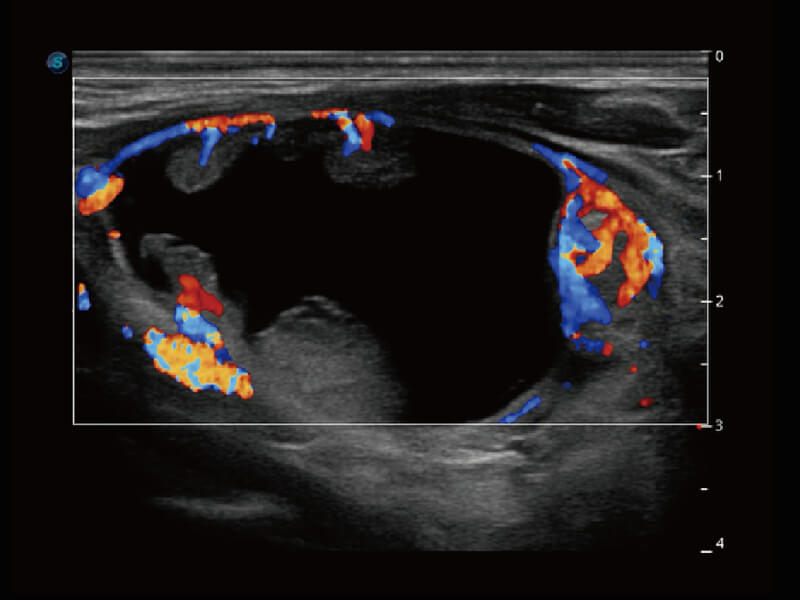

成像功能

S60探头工艺,从前端信号处理每一个环节采集无损声学数据,真实还原组织原貌,再现解剖细节。